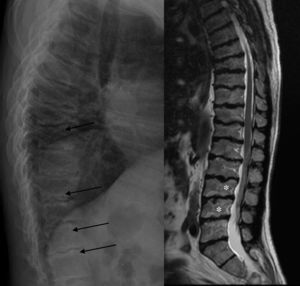

Manos en garra: imposibilidad para la flexión y la extensión máxima, sin que se objetive engrosamiento cutáneo ni afectación articular. Radiografía manos: huesos del carpo pequeños e irregulares (flecha) y falanges proximales anchas (línea acotada). La actitud en garra de los dedos produce una imagen de seudopinzamiento articular en IFP e IFD (flechas finas).

La ML III se manifiesta aproximadamente entre los 3 y 5 años de edad, con anomalías esqueléticas, alteraciones faciales, talla baja, inteligencia normal o retraso mental leve, opacidad corneal y escoliosis, a diferencia de otras formas de ML que sí tienen afectación visceral y un pronóstico vital sombrío en la infancia2,3. En la ML III la evolución es lenta, pudiendo alcanzar hasta la quinta década de la vida4. Las alteraciones óseas en la infancia pueden confundirse con artritis idiopática juvenil o esclerodermia, fundamentalmente por la afectación de las manos5,6. Los hallazgos radiológicos característicos de las manos son huesos del carpo pequeños e irregulares y falanges proximales relativamente anchas5 (fig. 1). En la columna lumbar, displasia vertebral con delineación irregular de los cuerpos vertebrales3, imágenes que se confirman en la RM (fig. 2). En la pelvis, displasia progresiva de las caderas, con acetábulos aplanados y destrucción de las cabezas femorales con coxartrosis secundaria2 (fig. 3).